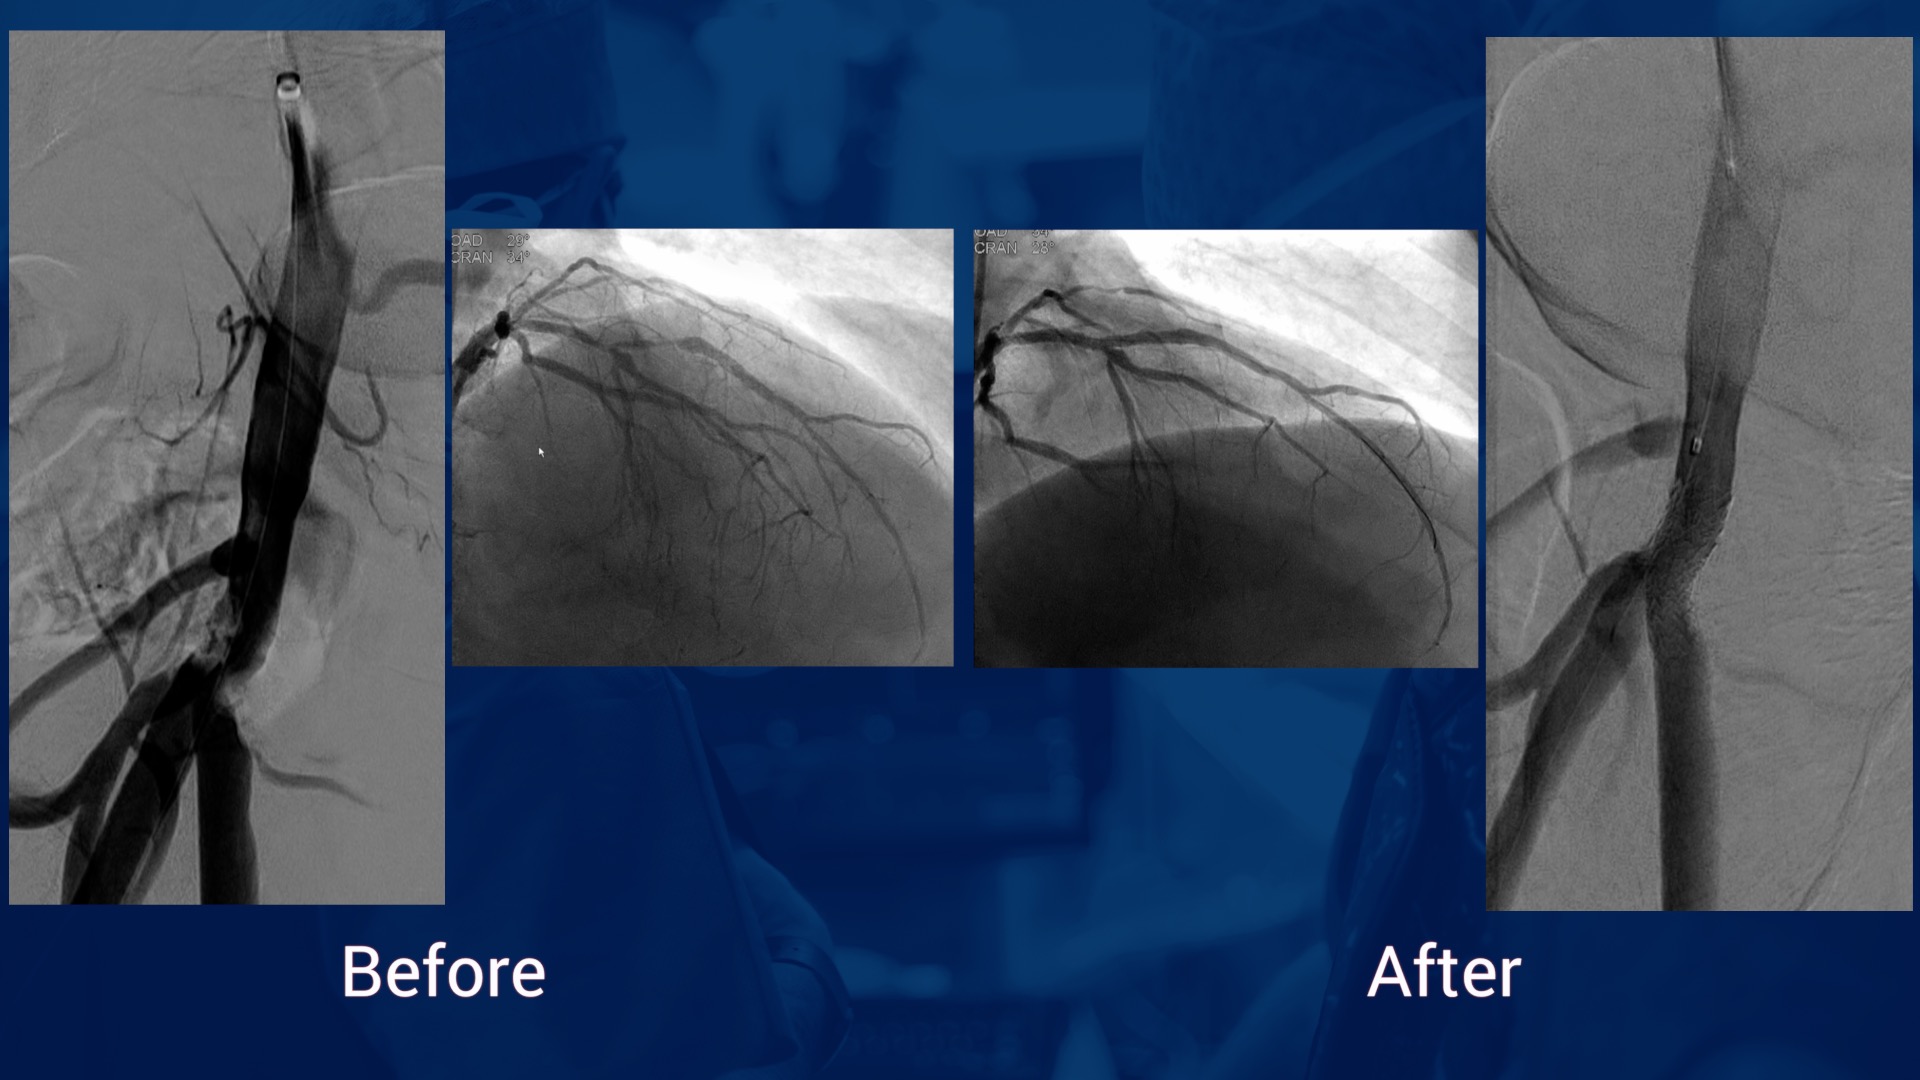

Patient polyvasculaire avec 3 lesions coronaires et une lesion de l’artère fémorale superficiell...

Dr Julien Lemoine & Dr Jérôme Brunet

Patient polyvasculaire avec 2 lesions coronaires et une lesion de l’artère fémorale commune droi...

Dr Lemoine & Dr Goyault